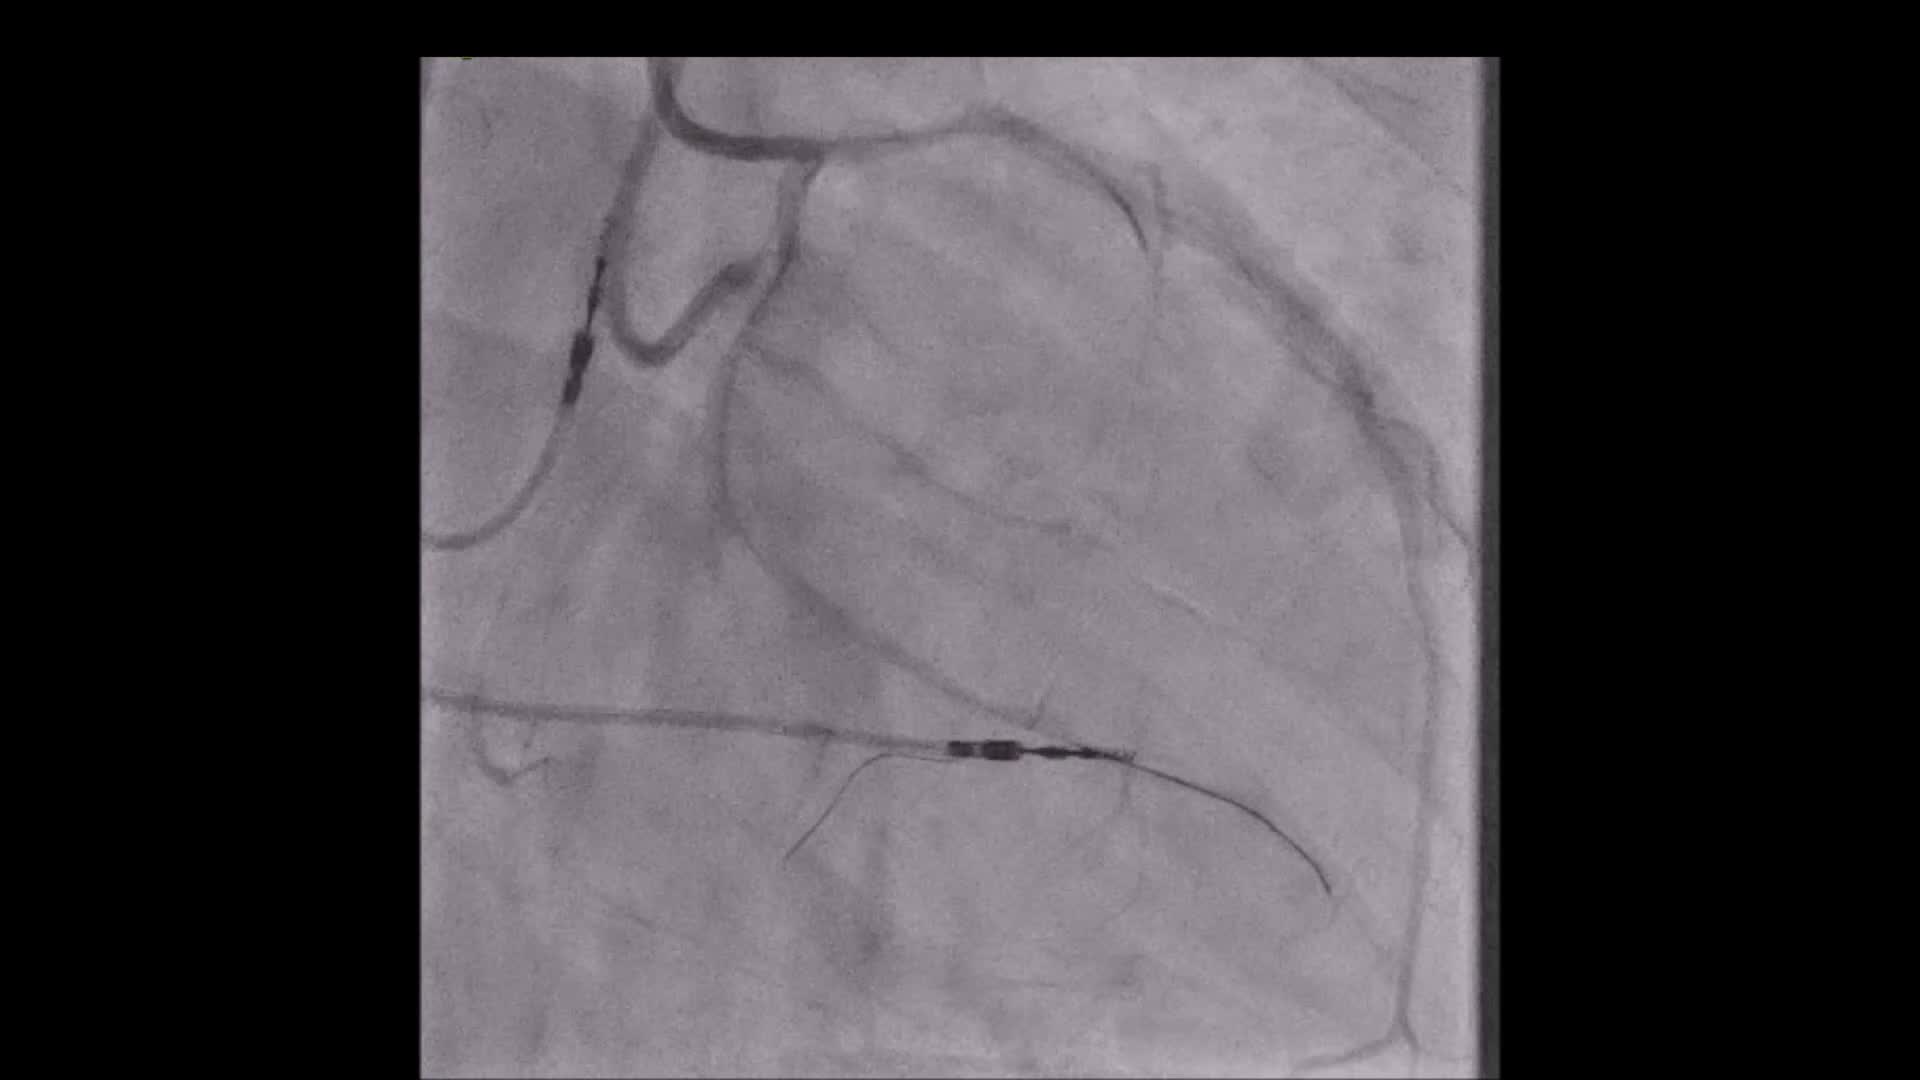

COMING THIS FRIDAY: Elliot Smith, Maximising efficiency in CTO PCI (using dedicated CTO equipment)